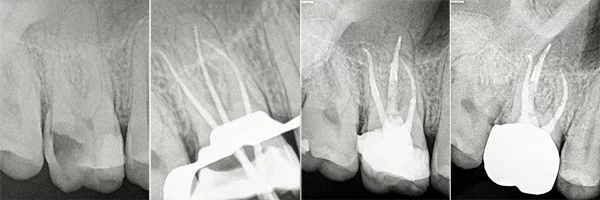

Root Canal in Morocco Before and Afters

Certified Endodontists with Microscope and Laser.

Check out our Before and Afters

Root Canals are done by an Endodontist and require the Specialist to make a hole through the enamel and dentin surfaces to gain access to the pulp chamber, where the Endodontist proceeds to remove the pulp, clean the pulp chamber and seal the chamber with gutta-percha. To ensure the long-term success of the tooth after a Root Canal an antibiotic is prescribed and a Post and Core Build-Up and Crown are recommended to prevent fractures or filtration of bacteria to the tooth.

A Post & Core Build-Up is a treatment that is done after a Root Canal and is needed to regain stability and tooth structure to that tooth. Once the pulp chambers are cleaned and sterilized a fiber post will be placed into the chamber to help absorb the shock from masticatory forces. The Post also helps to anchor the Core Build Up to the actual tooth.

A Post is a prosthetic device made of the metal alloy used to give strength and support to the toot structure after a Root Canal Therapy was performed and the due restoration is a Crown or a Bridge.

The Core Build-Up, made of composite material, replaces the nerve extracted in the Root Canal Therapy and supports either a Crown or the Retainer for a Bridge.

The Post & Core Build-Up require to give stability to the Crown or Bridge.